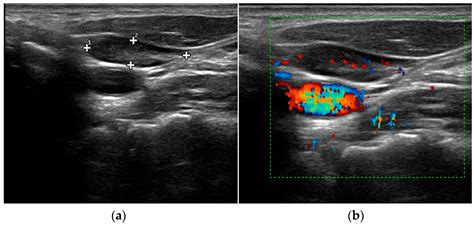

• Doppler Ultrasound: This technique uses sound waves to visualize blood flow within the parathyroid glands, helping to identify hypervascular tumors.

• Blood flow patterns within the glands, which can indicate the presence of tumors.

Abnormal findings may include enlarged parathyroid glands, the presence of adenomas, or other structural abnormalities. These findings are crucial for diagnosing conditions such as primary hyperparathyroidism, secondary hyperparathyroidism, and parathyroid carcinoma.